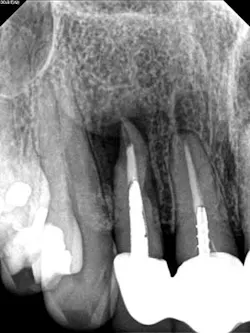

A 60-year-old male patient presented with a buccal swelling in the maxillary left anterior. Clinically the patient had a three-unit bridge connecting Nos. 7–9 (figure 1). The patient was happy with the esthetics and wanted to save his natural dentition. The recommendation was made to take a narrow-field CBCT scan to evaluate No. 7 in three dimensions. The CBCT scan showed that the apical disease had led to root resorption at the apical third of tooth No. 7 on the distal root surface (figure 2). This was invaluable information that allowed me to make the best approach to the root surface while keeping the osteotomy as small as possible. It also allowed me to have a three-dimensional view of No. 7 before even beginning the surgery, which helped to aid in proper root resection to conserve as much sound tooth structure as possible.

After root resection, root end prep and the placement of biologically compatible root end filling, the osteotomy was grafted (figure 3). Because of the size of the apical disease, along with the large cast post and the resorption, traditional nonsurgical retreatment was not a viable option for long-term success. With the aid of the CBCT imaging, it was already noted where the root end filling needed to be placed not only to seal the distal defect but to seal the true apical terminus.